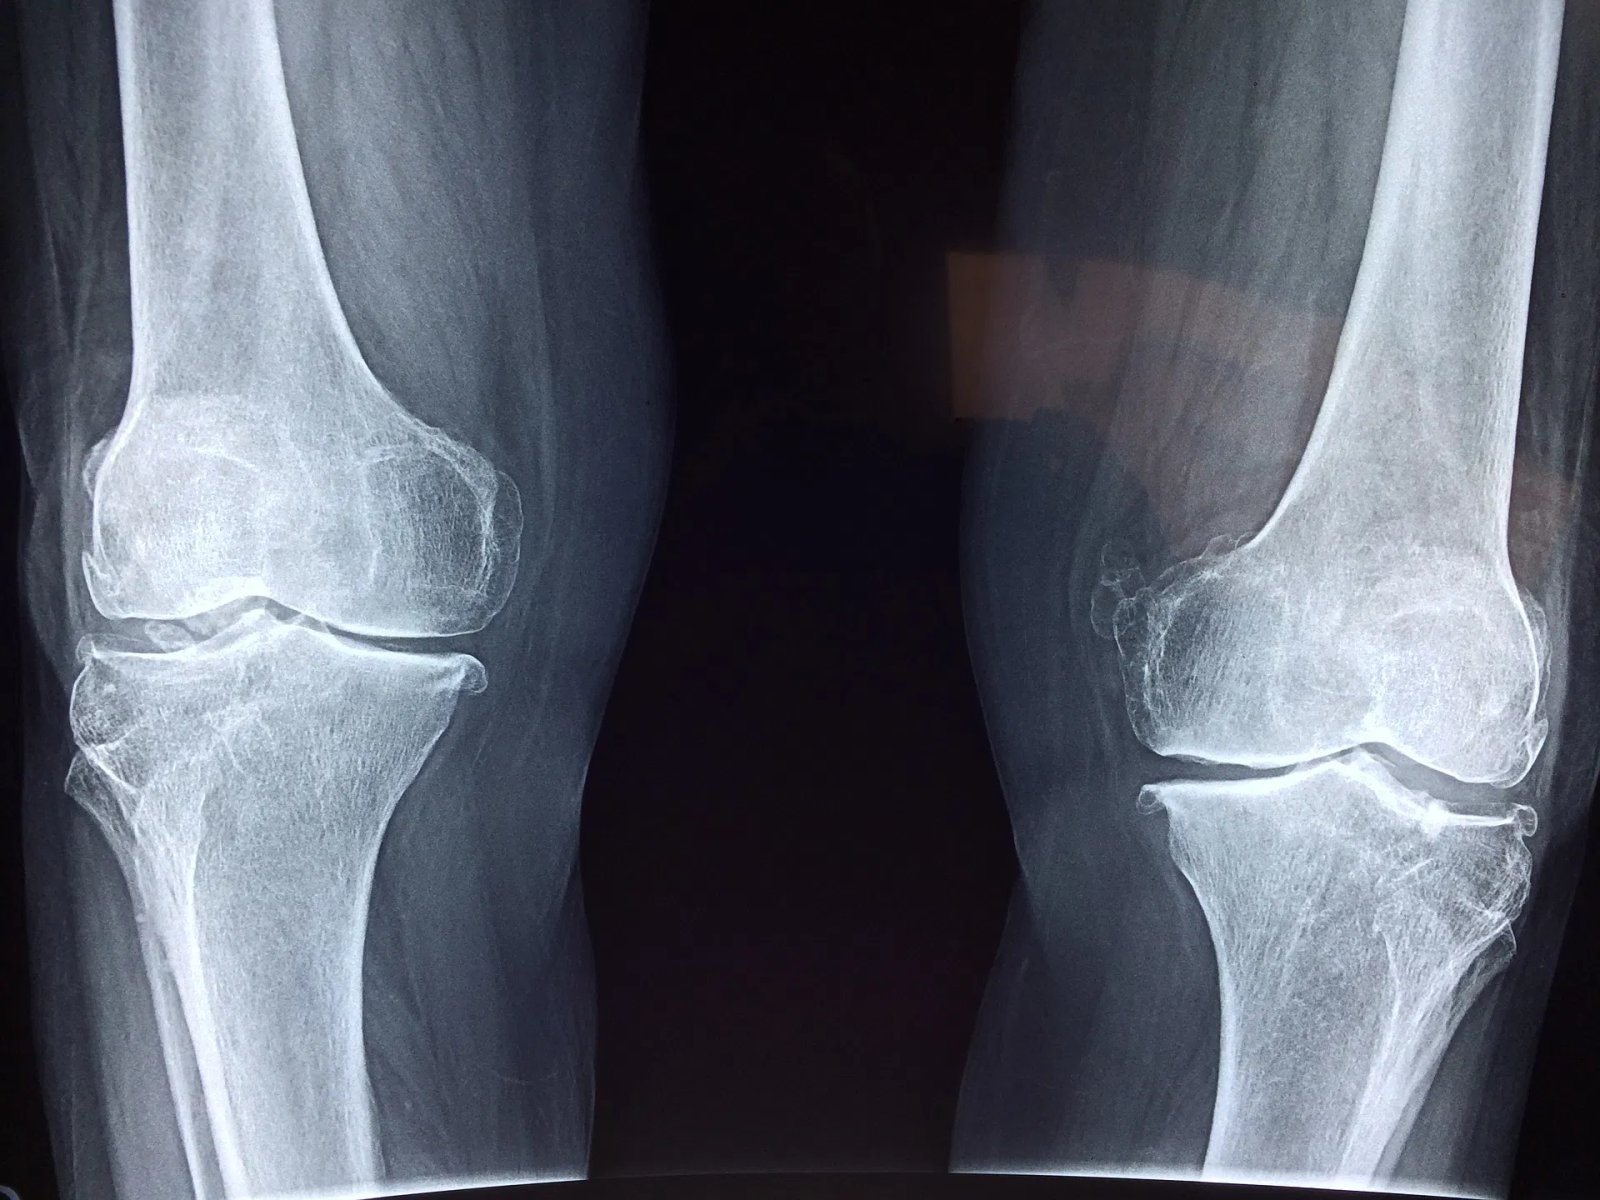

Osteoporosis Management

Osteoporosis is quite common among Indian population. Osteoporosis increases fracture risk.

At SOH we aim to identify patients at risk of osteoporosis, ensure early diagnosis and optimisation of treatment.

We are regularly conducting free BMD (Bone Mineral Density) camps for patients.

Patient education for prevention of osteoporosis, diet and life style modifications, physiotherapy are also suggested.